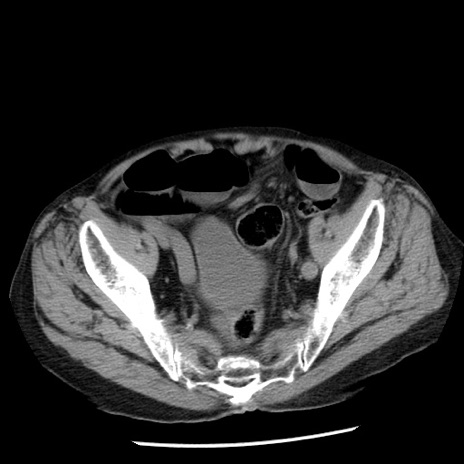

症例26(横断像)

【症例】80歳代男性

【主訴】嘔吐

【現病歴】昨晩2回嘔吐あり、今朝になっても嘔吐あり。来院。

【既往歴】胃潰瘍

【身体所見】意識清明、BT 37.6℃、BP 166/95mmHg、HR 100bpm、SpO2 97%、腹部:平坦・軟、腸蠕動音聴取良好、圧痛なし。

【データ】WBC 21900、CRP 1.46